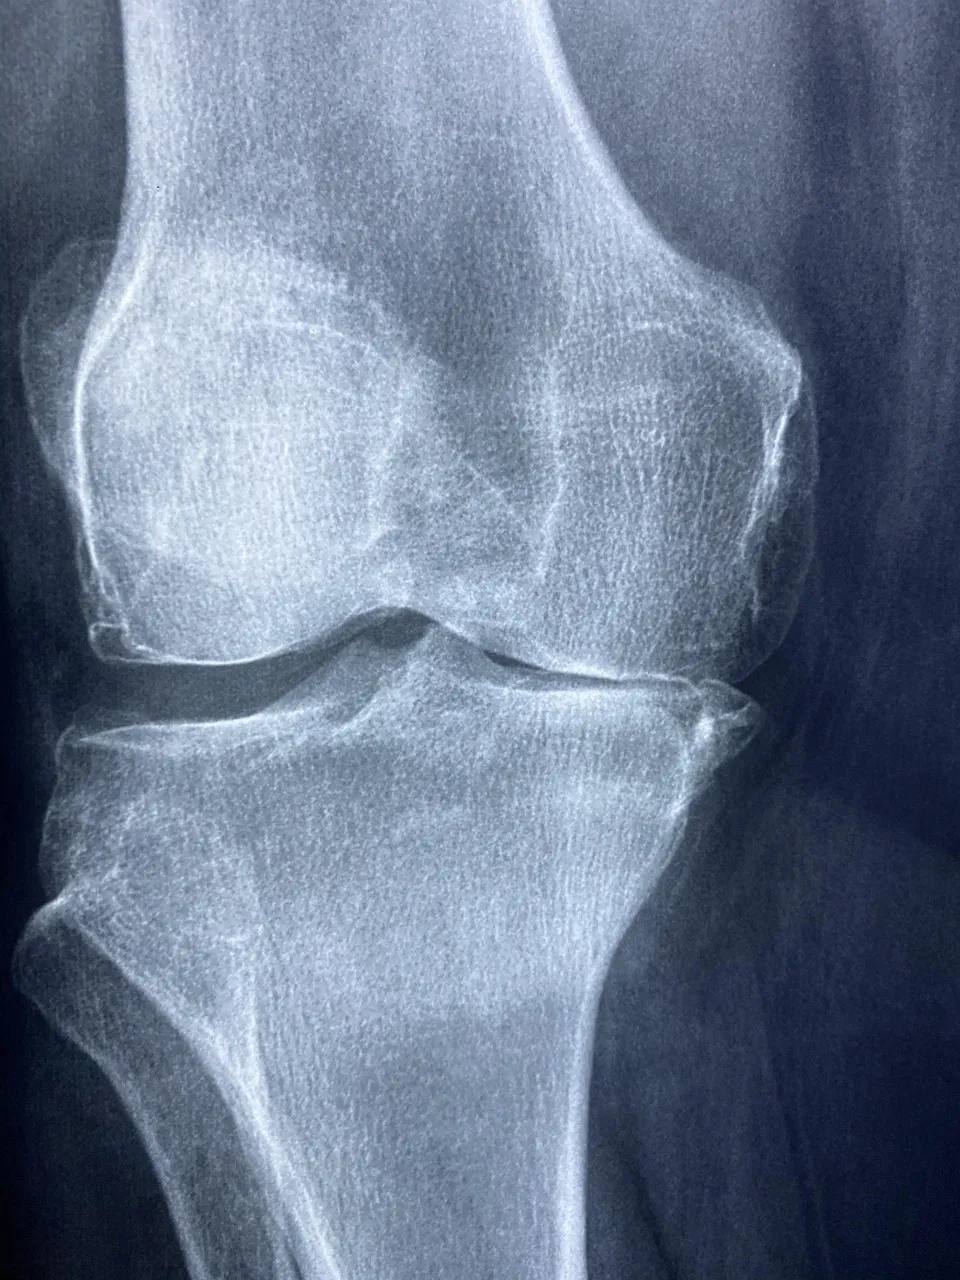

보스웰리아 효능 ① 관절염 개선 및 염증 완화

보스웰리아 효능 중 가장 대표적인 건 단연 관절 통증 완화입니다.

보스웰리아에는 ‘보스웰릭산(Boswellic Acid)’이라는 강력한 항염 성분이 들어 있는데,

이 성분이 관절 내 염증을 유발하는 효소(5-LOX)의 작용을 억제해줍니다.

보스웰리아 효능 ② 관절 연골 보호

보스웰리아는 단순히 통증만 줄이는 게 아니라,

관절을 구성하는 연골 손상을 예방해주는 역할도 합니다.

한 연구에 따르면, 보스웰리아 추출물을 8주 이상 꾸준히 섭취한 사람들의 연골 파괴 지표가 개선되었다고 합니다.